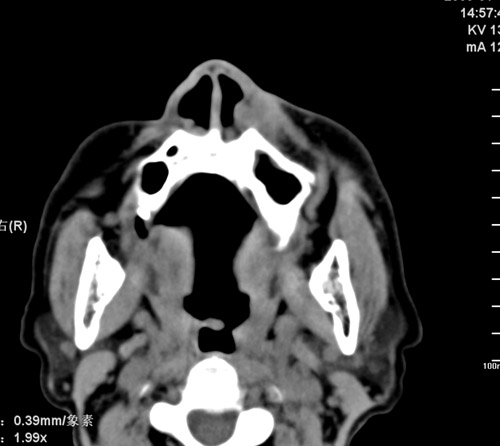

标题: CT17755:女,74 左鼻旁肿胀半年,临床以左上颌窦旁占位行CT [打印本页]

标题: CT17755:女,74 左鼻旁肿胀半年,临床以左上颌窦旁占位行CT

ct考虑鼻前庭囊肿 或鼻翼基底部慢性炎症,左上颌窦少许炎症 请指教

1)考虑左侧鼻前庭囊肿并感染。2)双侧上颌窦炎。

左侧鼻前庭囊肿并感染。双侧上颌窦炎。支持